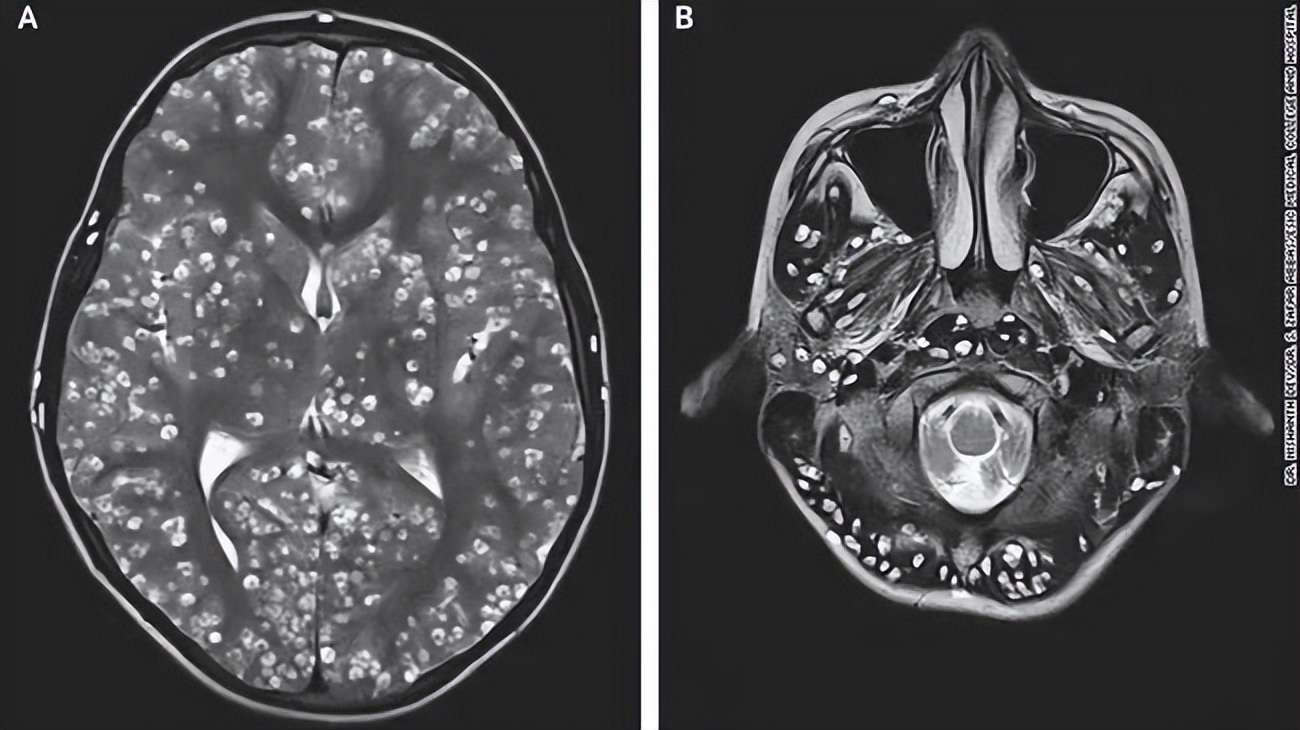

neurocysticercosis

脑囊虫病

术语缩写脑囊虫病(neurocysticercosis,ncc)同义词囊虫病定义由猪肉

囊虫病:一种常见的中枢神经系统寄生虫感染

全身长满密密麻麻的凸起,看到大脑 ct 后医生慌了